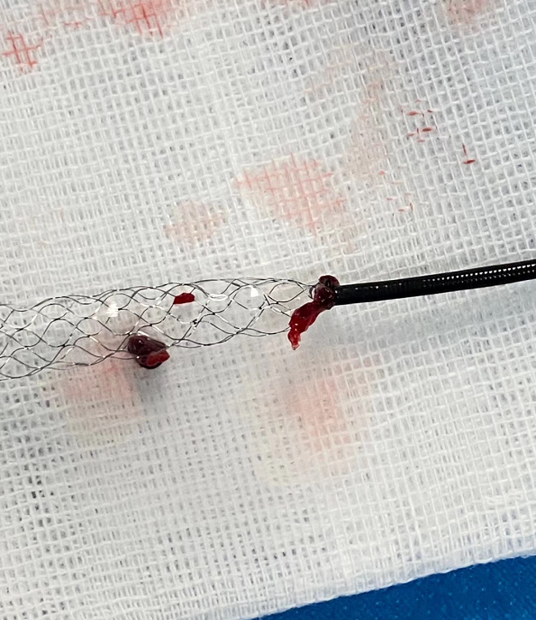

病因:心源性栓塞。

原因:血栓质韧。

方式:支架取栓。

支架规格齐全,本病例4*30支架,支架足够长,增加血栓夹持力,提高开通率。

该病例是心源性栓塞,血栓质韧,本例选用蛟龙4*30mm更长的取栓支架,更长长度提供更大表面积接触血栓,以独特的侧边螺旋开放结构,帮助快速高效一次三级再通。一篇研究回顾性分析了2011年6月到2017年3月使用直径4mm取栓支架及球囊指引导管作为首选治疗策略治疗ICA、MCA急性闭塞的病例。该研究中,4×30mm和 4×40mm被定义为长支架,4×20mm被定义为短支架。主要的临床结局是一次性取栓血管成功再通率(mTICI 2b/3)。研究共纳入420例患者,其中221例(53%)患者使用长支架,119例(47%)使用短支架。相对于短支架,长支架组一次性取栓血管开通率(62% vs 50%;P=0.01)和最终血管开通率(mTICI2b/3,98% vs 94%;P=0.01)更高。长支架一次性取栓成功开通率高的原因,可以从以下几方面来解释:长血栓会提供更大的表面积与取栓支架接触包裹血栓,也会在取栓过程中使张力均匀分布,在血管路径扭曲或者躁动的病人中,长支架通过增加可接受的误差范围来实现精确释放。更长的支架会增加取栓装置向血栓远端延伸的移动力,同时,在支架首个与血栓接触的网孔抓捕血栓失败的情况下,可以增加血栓取出的机会。[1]因此,通桥医疗即将上市的蛟龙4*30mm取栓支架在临床上的广泛应用值得期待。